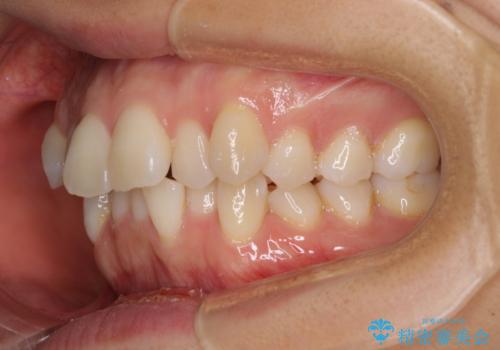

前歯のデコボコを抜歯矯正で改善 メタル装置で費用を抑える

- 前歯のデコボコと口元の突出感を気にして来院された患者様です。

非抜歯矯正ではデコボコを解消することでより口元が突出してしまうため、上下左右の小臼歯4本の抜歯を行い、ワイヤー装置による矯正治療を行うこととしました。

もう少し口元の突出感を改善したかったのですが、舌の突出癖が影響し下顎前歯が唇側に押させる仕上がりとなりました。